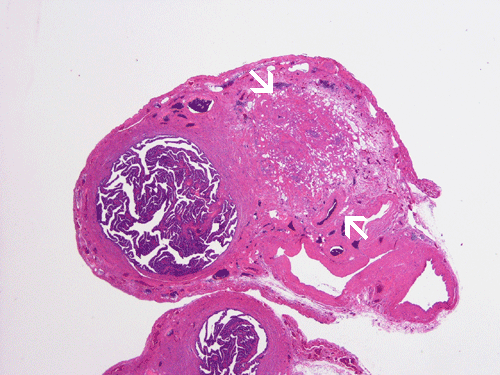

On scanning magnification, there is a round lesion in tissue around the fallopian tube (arrows in Panel A). The lesion does not invade into the tube nor distort or compress the tube. The cross sectional dimension is about the same diameter of the fallopian tube. On low and medium magnification, the lesion is composed of a collection of small microcysts intermingled with the smooth muscle bundles of the wall of the fallopian tube (Panel B and C). On higher magnification, the cyst or gland like spaces are lined by epithelioid to spindle cells with bland nuclei and an abundant amount of amphophilic cytoplasm (Panel D and E). The spindle cells are positive for calretinin, cytokeratin 5/6, and inhibin (Panel F, G, and H).

Macroscopically, ademonatoid tumors are well-circumscribed nodules with a gray-white cut surface. With the mesothelial origin, it would not be surprised that they are typically found in a subserosal location.